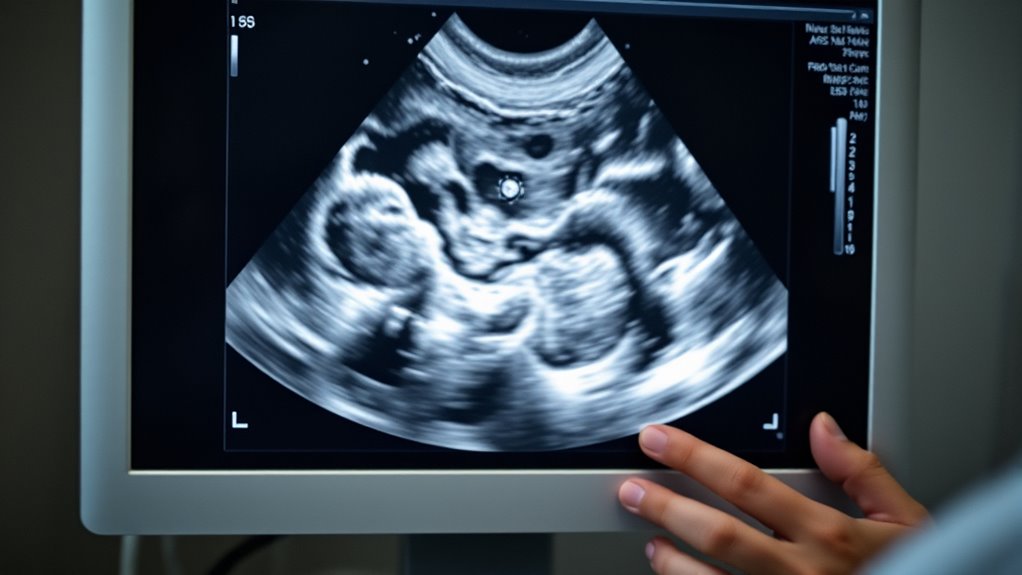

Ultraschall unterscheidet effektiv zystische von soliden Massen, indem es die akustischen Eigenschaften analysiert und somit sofortige, Echtzeit-Informationen über die Merkmale der Läsion liefert. Zysten erscheinen typischerweise einkernig, mit klar abgegrenzten Grenzen, hintergrundverstärkung und runden oder ovalen Formen, was den BI-RADS-Kriterien für einfache Zysten entspricht. Solide Tumoren weisen oft unregelmäßige Ränder, heterogene interne Schallwellen und variable Formen auf. Ultraschall hilft auch dabei, abnormale axilläre Lymphknoten zu identifizieren, indem er Größe und Morphologie beurteilt, was für die Stadieneinteilung entscheidend ist. Mit Ultraschall können Sie auch Biopsien oder Feinnadelaspirate präzise durchführen, was die diagnostische Genauigkeit erhöht. Zudem unterstützt es die Behandlungsplanung, indem es postchirurgische Veränderungen überwacht oder die Strahlentherapie leitet. Die Integration von Achtsamkeitstechniken in die diagnostischen Verfahren kann medizinisches Fachpersonal dabei helfen, den Fokus zu bewahren und Stress während komplexer Eingriffe zu reduzieren. Dieses dynamische Bildgebungsinstrument verbessert Ihre Fähigkeit, Brustanomalien schnell und genau zu beurteilen, was zu einer frühzeitigen Erkennung und angemessenen Behandlung beiträgt.

Unterscheidung von zystischen und soliden Massen

Eines der Hauptmerkmale der Ultraschalluntersuchung liegt in ihrer Fähigkeit, zwischen zystischen und soliden Brustmassen schnell und effektiv zu unterscheiden. Dies hilft Ihnen, die Natur der Läsion zu bestimmen und die weitere Behandlung zu lenken. Zystische Läsionen erscheinen typischerweise anechoisch mit klaren, glatten Grenzen und zeigen eine posteriore akustische Verstärkung. Solide Massen weisen oft interne Echos, unregelmäßige oder glatte Ränder auf und können erhöhte Durchblutung zeigen. Um diese zu unterscheiden, achten Sie auf:

- Anechoische, flüssigkeitsgefüllte Erscheinung bei Zysten

- Gut abgegrenzte Ränder, die auf benigne Zysten hinweisen

- Interne Echos oder komplexe Merkmale, die auf solide oder komplizierte Zysten hindeuten

- Erhöhte Durchblutung sichtbar mit Doppler, was auf solide oder verdächtige Läsionen hinweist

Mithilfe dieser Ultraschallmerkmale können Sie Brustmassen genau klassifizieren und entscheiden, ob weitere diagnostische Schritte, wie eine Biopsie, notwendig sind.